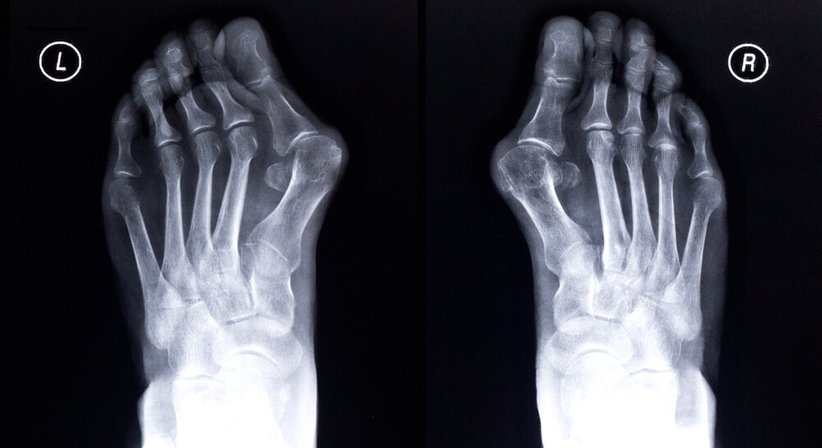

Hallux valgus

Der Hallux valgus ist die häufigste Fehlstellung des vorderen Fußes. Es handelt sich um eine Fehlstellung des Großzehengrundgelenks, durch welche die Großzehe nach außen abweicht (nach außen gerichteter Schiefstand der Großzehe). Charakteristisch für einen Hallux valgus ist eine Vorwölbung im Bereich des Großzehengrundgelenks, wo das häufig schmerzhaft entzündete und geschwollene Mittelfußköpfchen hervortritt und beim Gehen schmerzhaft gegen den Schuh drückt. Anfangs ist ein Hallux valgus für Betroffene häufig nur ein kosmetisches Problem. Mit der Zeit kann die Fehlstellung jedoch sehr schmerzhaft und zu einer großen Belastung werden und neben Schmerzen zu verschiedenen weiteren Beschwerden und krankhaften Veränderungen im Bereich des Fußes führen.